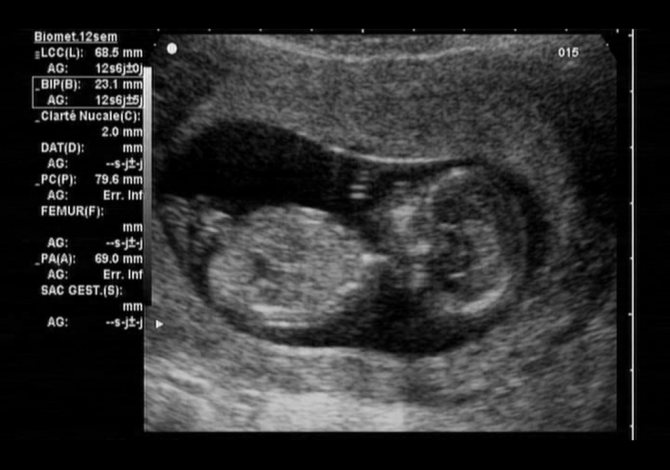

Существует перечень наиболее важных показателей развития плода, которые и легли в основу расшифровки заключения УЗИ. К таковым относятся: КТР, РАРР-А, ЧСС, БПР, ТВП, ХГЧ, НК и пр. Для того чтобы установить точный прогноз течения беременности, специалисту необходимо сравнивать личные данные своей пациентки, полученные при первом скрининге, с утвержденными нормативами, которые прописываются в соответствующих таблицах.

При первом скрининге на экране монитора можно увидеть плод целиком, его размеры ещё настолько малы, что позоляют разглядеть малыша «от макушки до пяточек»